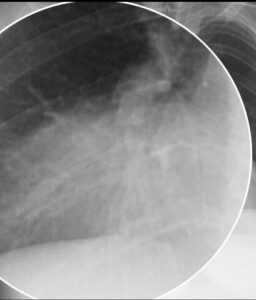

Lokalisation bei unklarer Verschattung

Wird ein pathologischer Schatten auf einem Thoraxbild beobachtet, kann das Silhouettenzeichen helfen, zwischen Mittellappen- und Unterlappenprozessen zu unterscheiden.